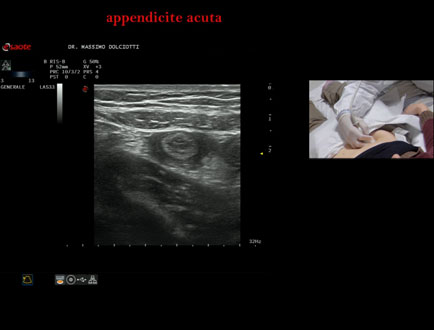

Data inserimento: 21/01/2025

Ecografia del: 16/01/2025

Strumento: Esaote MyLab Eight

Sonda: Convex Multifrequenza 1-8 MHz e Lineare Multifrequenza 4-15 MHz

Età Paziente: M 45 anni

Motivazione dell'esame: da 2 giorni dolore in sede ileo-cecale

Commento all'esame: le immagini ed il video documentano in sede ileo-cecale, il verme appendicolare di spessore aumentato pari a 7,6 / 8,1 mm ( v.n. < 6 mm), da ricondurre ad appendicite acuta.

Conclusioni: appendicite acuta (acute appendicitis).

Presentazione: Dr. Massimo Dolciotti - Ancona